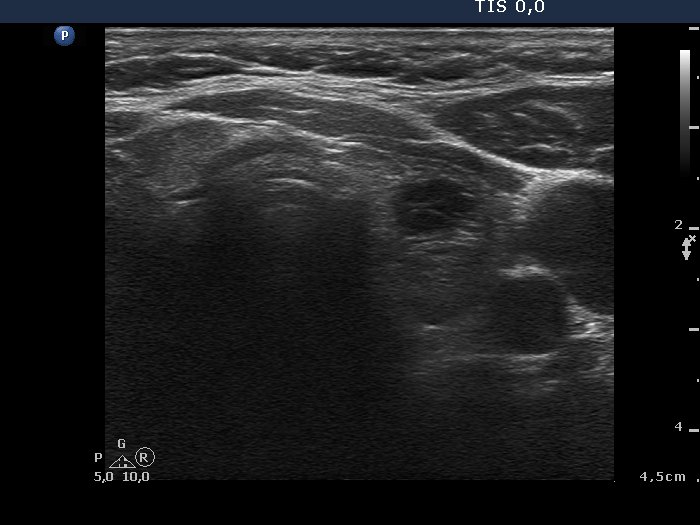

Extrathyroidal spread - case conp 007 (ultrasonographic picture 6)

Left lobe, transverse view. The lobe is minimally hypoechogenic and inhomogeneous. There is a hypoechogenic lesion in the central part of the lobe.